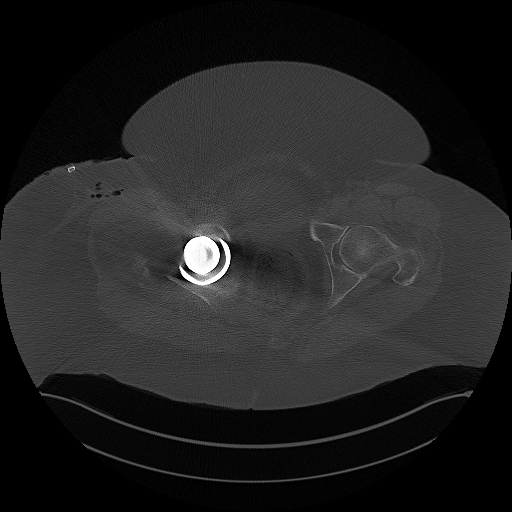

CT Becken + Überweisung zur weiteren Abklärung

04.03.2025

CT Becken

853 Bilder in 4 Serien | 86 MB

DICOM

CT-Untersuchung mit 4 Serien (853 Bilder)